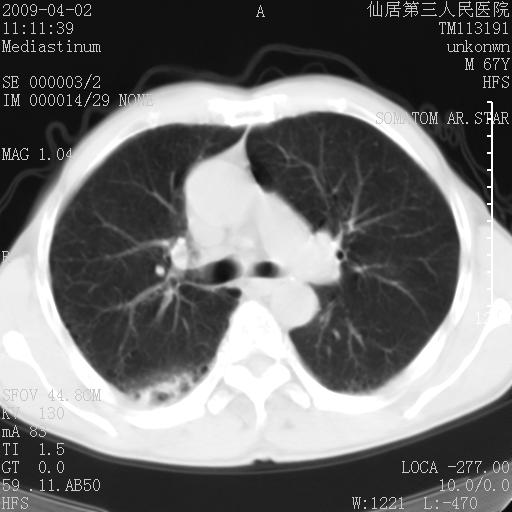

患者老年男性,乏力畏寒来诊,摄胸片示右下肺感染性病变,抗炎两周后复查胸片,无好转有进展。

后做ct平扫表现如下:

考虑右肺炎症可能性大,不除外细支气管肺泡癌

是否还要考虑肺间质纤维化,建议hrct扫描。

考虑间质性肺炎。

病灶呈蜂窝征,纵隔多个淋巴结肿大;肺泡癌需考虑

我认为普通的感染应该可以除外,间质性肺炎可能性较大,但如何解释纵膈的淋巴结肿大呢

考虑双肺间质性改变(间质纤维化?)伴右肺下叶感染。